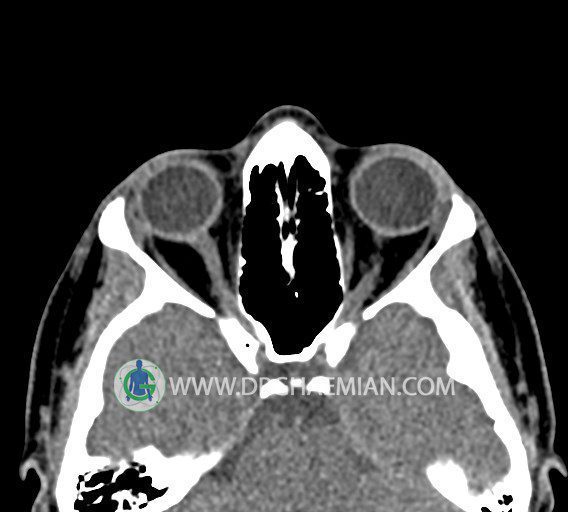

در HRCT اسپيرال از سينوس هاي پارانازال مقاطع کرونال و آگزيال ( 16 اسلايس و مقاطع ظريف 1.5 mm بدون فاصله ، با پنجره استخواني و نسج نرم ) :

– اوستيوم فرعي در ديواره مديال سينوس ماگزيلاري راست

مشهود است .